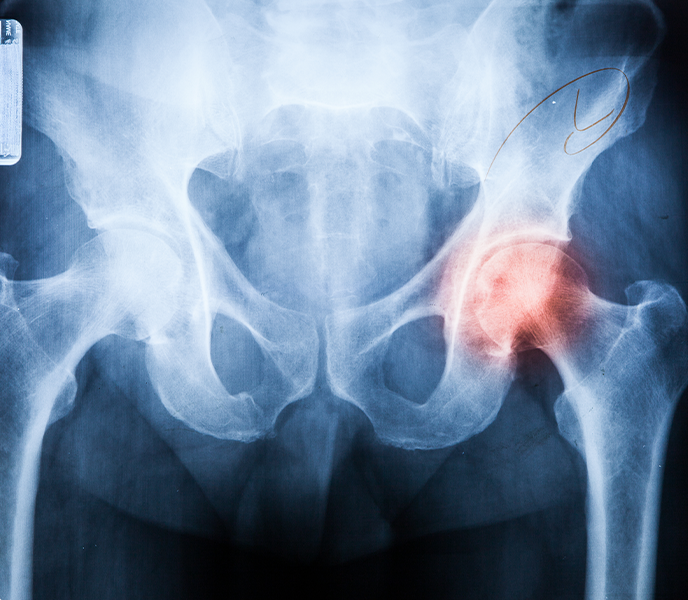

골반염 클리닉

골반염은 작은 증상도 놓치지 말고 초기에 치료해야 합니다.

골반통/요통

골반과 하복부에

통증이 나타납니다.